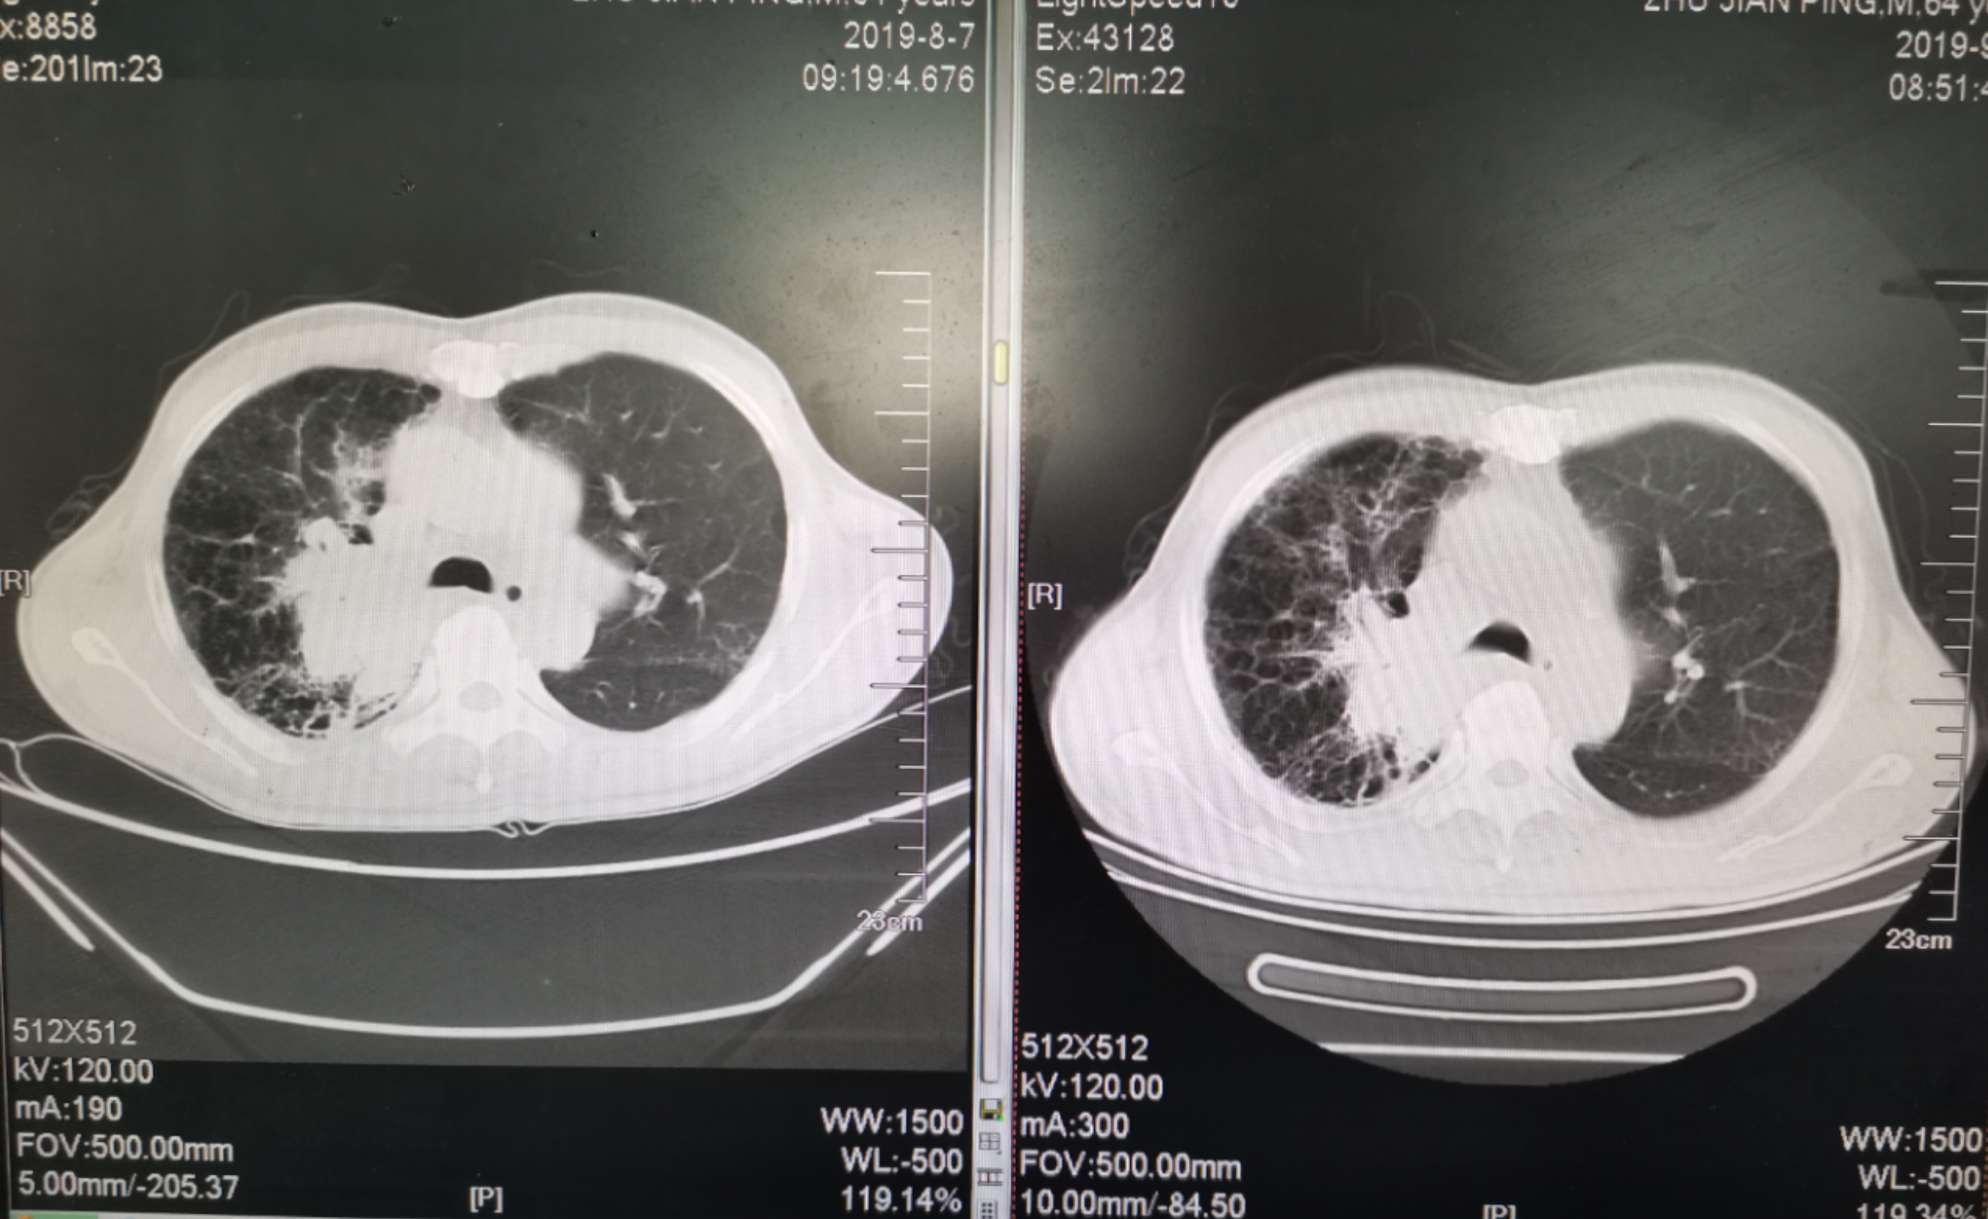

二化联合一k后复查ct对比

左边是上月化疗前的,右边是昨天拍的,今天上了第二次k药,准备明天第三期化疗。

我自己对着拍的,切面对的不是很准确,但大致上看的出来明显小了。